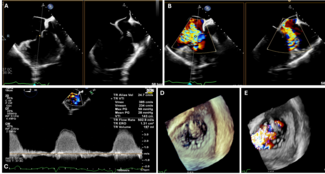

Ka-chun Un, MBBS, MRes; Cheung-chi Lam, MBBS; Hay-son Chen, MBBS; Chun-ka Wong, MBBS; Ho-on Alston Conrad Chiu, MBBS; Yui-ming Lam, MBBS; Kwong-yue Eric Chan, MBBS

A 36-year-old man with unrepaired double inlet and double outlet right ventricle, severe pulmonary stenosis, and dextroversion, who was on the heart transplant waiting list, presented with acute heart failure.